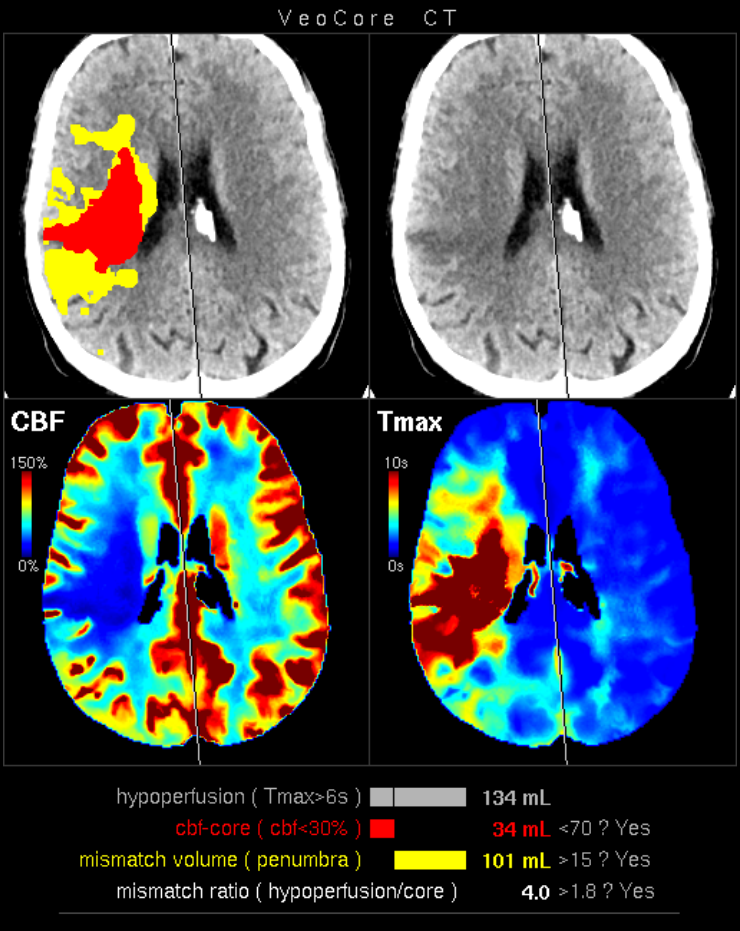

Furthermore mRay is capable of performing image processing tasks such as finding, visualizing and quantifying anomalies in tissue. In particular the image analysis module mRay VEOcore may be used to perform an automated processing of brain images from imaging modalities such as CT, CT-Perfusion, or MRI including a Diffusion Weighted Imaging (DWI) Module. As a result, changes in contrast over time are visualized as colored perfusion maps, including flow related parameters and tissue blood volume quantification.

The perfusion analysis of brain imaging data visualizes and quantifies tissue that is less supplied with blood (penumbra), oxygen deprived tissue caused by obstructed blood flow (core tissue) and the mismatch ratio between the two. The calculated values can be used to support decision making based on an assessment of the extent of tissue damage.

16.1. Overview

VEOcore is a fully automated image processing tool to calculate quantitative measures of affected brain tissue and healthy tissue. Therefore, this manual covers the instructions on how to interpret the results. It’s an extension the mRay Server application and the results can be viewed inside the mRay Client. Furthermore processed results can be automatically forwarded to the PACS.

16.2.1. Computed Tomography (CT))

-

CT perfusion (VPCT)

Repeatedly acquired volumes of low-dose CTs acquired during injection of a contrast bolus. This series is often called VPCT (Volume-Perfusion-CT). -

Non-contrast native CT image (optional)

Native image before contrast injection with a reconstruction kernel optimised for brain tissue. Sending this image is optional, but recommended. If sent together with the VPCT, it is used as background for the overlay with the segmented core and mismatch volume.